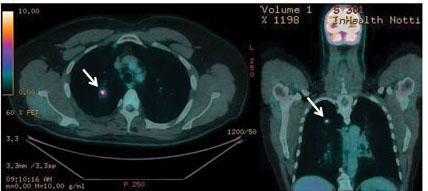

Investigations

The initial investigation of choice in secondary care remains a computed tomography (CT) scan of the chest and abdomen, followed by PET-CT scanning in those deemed suitable for potentially curative (radical) treatment, see figure 1. This is both to ensure staging is as accurate as possible and to direct diagnostic sampling.